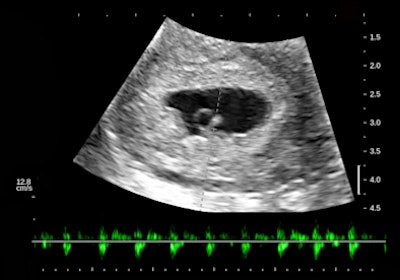

There is a intrauterine pregnancy with a (right) corpus luteum with an intact vascular margin. A regular heart rate of 122 beats per minute implies a 6.0-week stage. The Doppler pattern has separate filling and ejection phases. The decidual boundary is thick and well implanted. But there was another unexpected finding when looking at the left ovary:

![]() |

The findings in these views of the distal descending left colon are typical and classic for active ulcerative colitis. The submucosa is thick, reflective, and hyperemic. Some divots can be seen along the mucosa and one transverse section shows a tiny submucosal cyst. What do you think a transabdominal exam would have shown? Would that study have served the best needs of this patient?